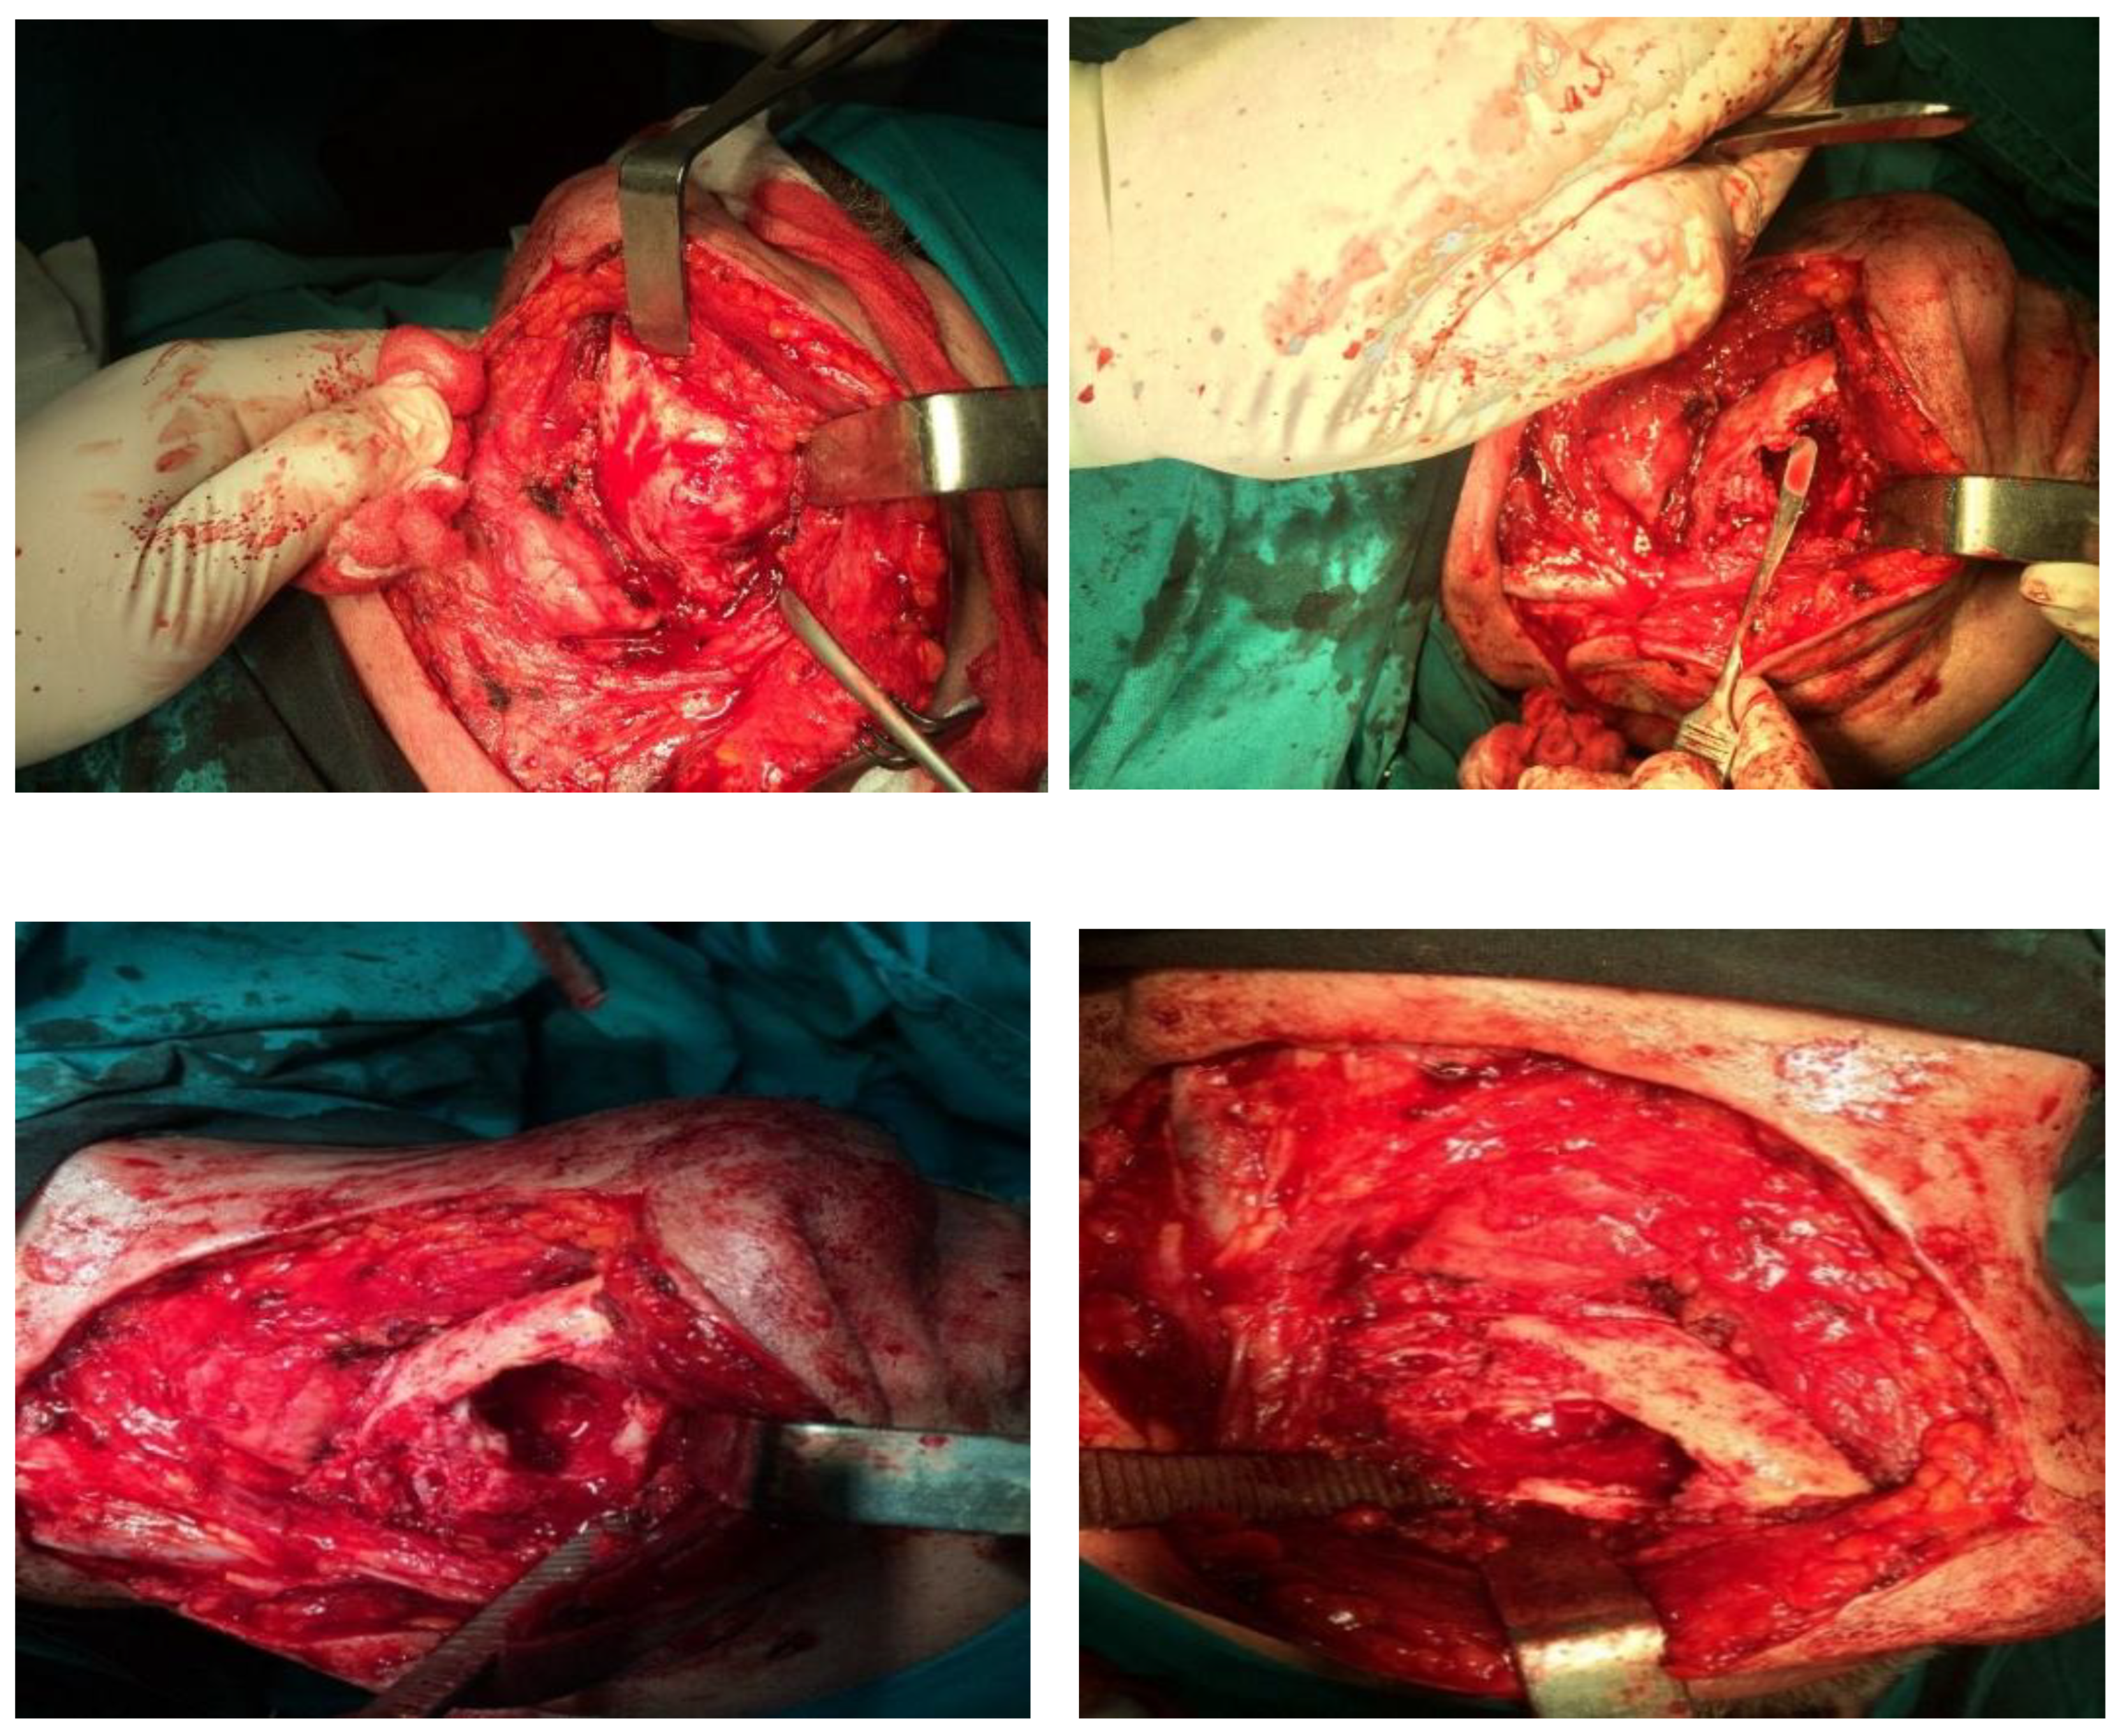

2.2. Methods

3. Results